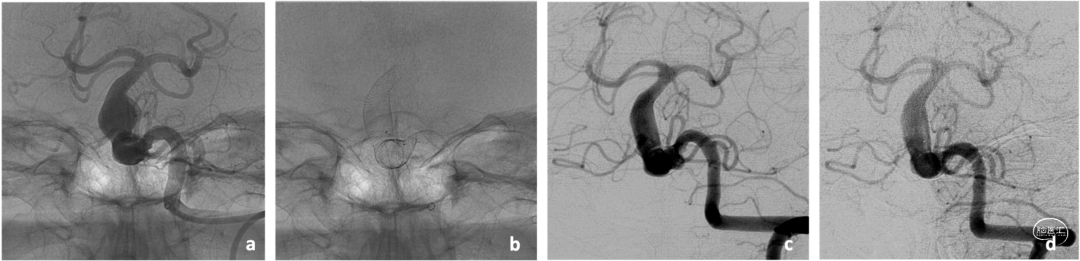

5例患者均为后循环巨大动脉瘤。每个患者植入2-3个不同型号Accero®-Rex支架,支架植入过程中无技术并发症发生。术后CT或MRI对照显示其中3例患者仅有轻微的局灶性缺血,这些患者的神经功能无明显的临床恶化。在患者2中,植入支架型号为7x60mm+7x30mm。支架覆盖动脉瘤后3个月的随访影像中,动脉瘤直径之前的11×11mm明显减小到6×6mm(图1示);在8个月随访时,动脉瘤大小较3个月随访时未发生显著变化。患者5随访显示,动脉瘤大小在3个月时无明显变化。2例患者死于与手术干预无关的其他原因(患者1死于心脏合并症和患者3死于肺部感染),患者4仍在随访中。

图1. 患者2植入Accero®-Rex支架前后血管造影(a、b)。3个月时随访造影(c)显示动脉瘤形态较前(a)明显减小,在8个月随访时与3个月随访时动脉瘤形态无明显变化,且没有支架内狭窄或血栓形成的征象。